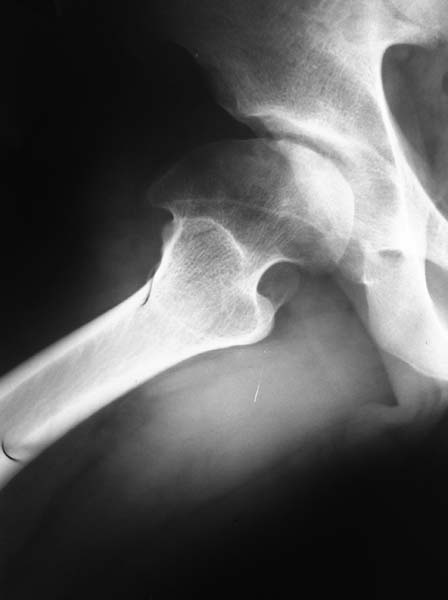

Здесь комбинированная патология тазобедреннего сустава, связанная с высокостоящим вертелом и отсутствием (ротирована?) шейкой. А на стороне вертлужной впадины диспластический сустав. Обычно высоко расположенный вертел приводит к уменьшению силы мышц абдукторов, но отстутствие шейки привело к вертикальному расположению сил в суставе. Боли появляются из-за вертикального давления, а неровные контуры головки приводят к ограничению движений в суставе. Такое состояние быстро изнашивает сустав, и больные в молодом возрасте заканчивают тотальным протезированием.

Для оценки пригодности сустава надо сделать снимки во внутренной и наружной ротации, а также с отведением и приведением каждого сустава. Сравнительные снимки покажут возможный подвывих и укорочение, а также состояние суставной щели. 3D Компьютерная Томография покажет возможную ротацию шейки.

Представленный случай имеет схожесть...., и последний снимок после 2 х лет.